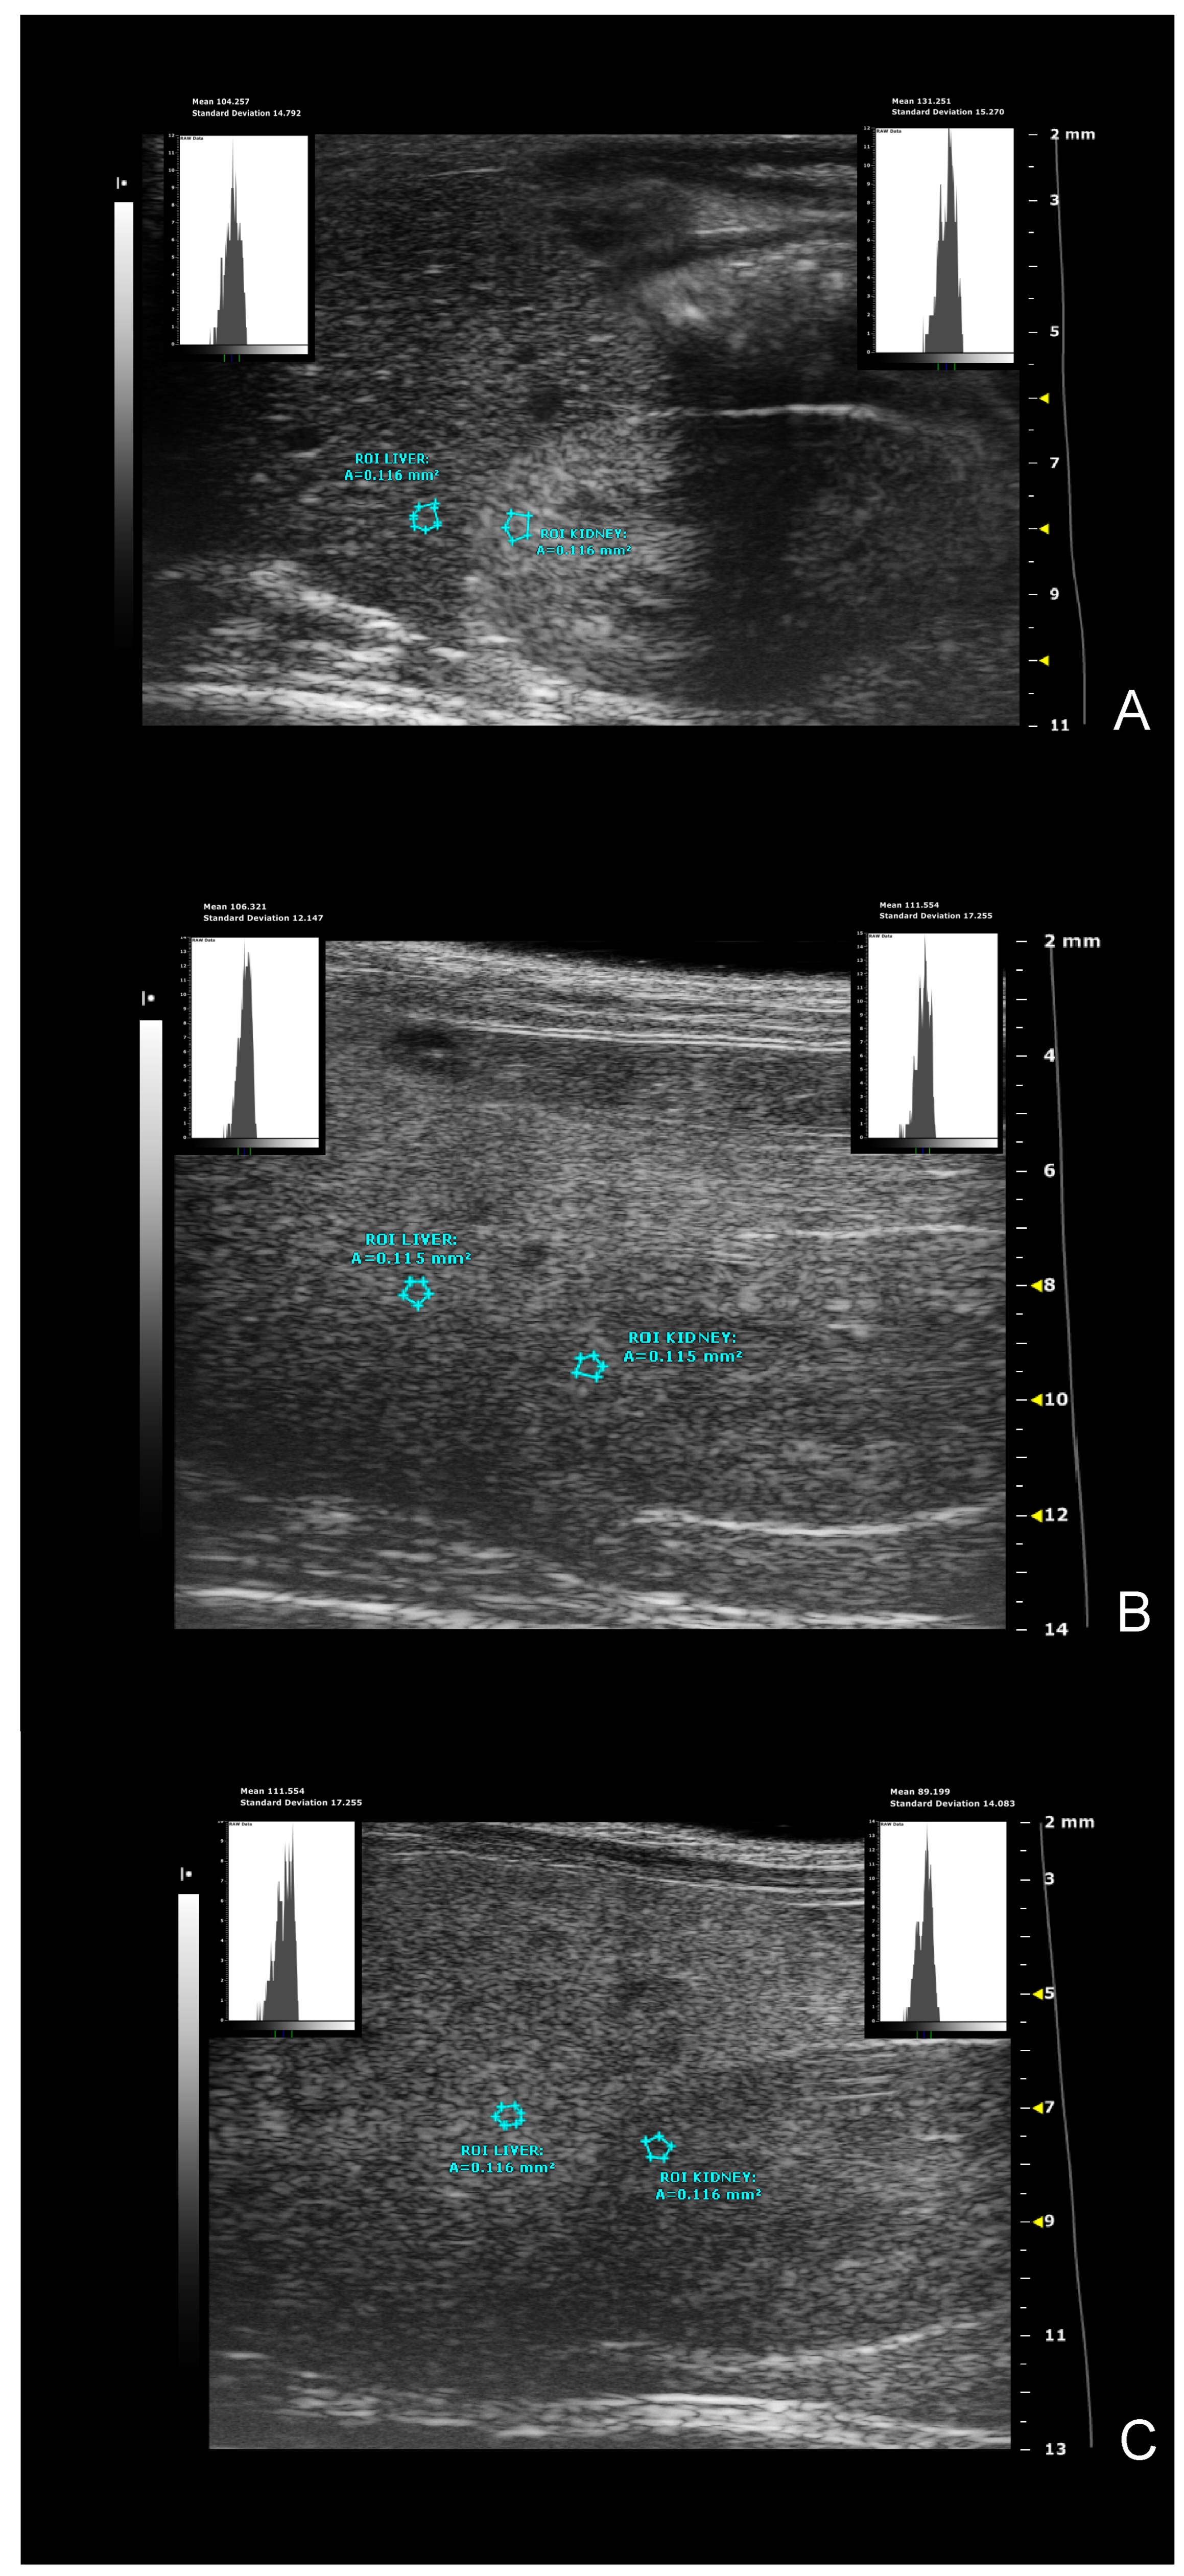

- hepatic-renal ratio (HR): This measurement is based on the hypothesis that a higher liver fat content causes an increase in US liver echogenicity. Longitudinal view was acquired in order to have both the liver (caudate lobe) and the right kidney clearly visualized. Liver echogenicity was compared with that of the renal parenchyma, to normalize differences in the overall US gain value used for the acquisitions. Two regions of interest (ROI, (0.1±0.02 mm2) were manually drawn: the first one was placed in the liver parenchyma avoiding focal hypo and hyperechogenicity; the second was positioned in correspondence with a portion of the renal cortex devoid of large vessels, along the focusing area of the image, at the same distance from the probe and along the focus area of the image to avoid distorting effects in ultrasonic wave patterns. HR values were obtained dividing the mean grey level of the hepatic ROI for that obtained for the renal one (Pixel intensity = average intensity/mm2 [a.u.]) [7,46].